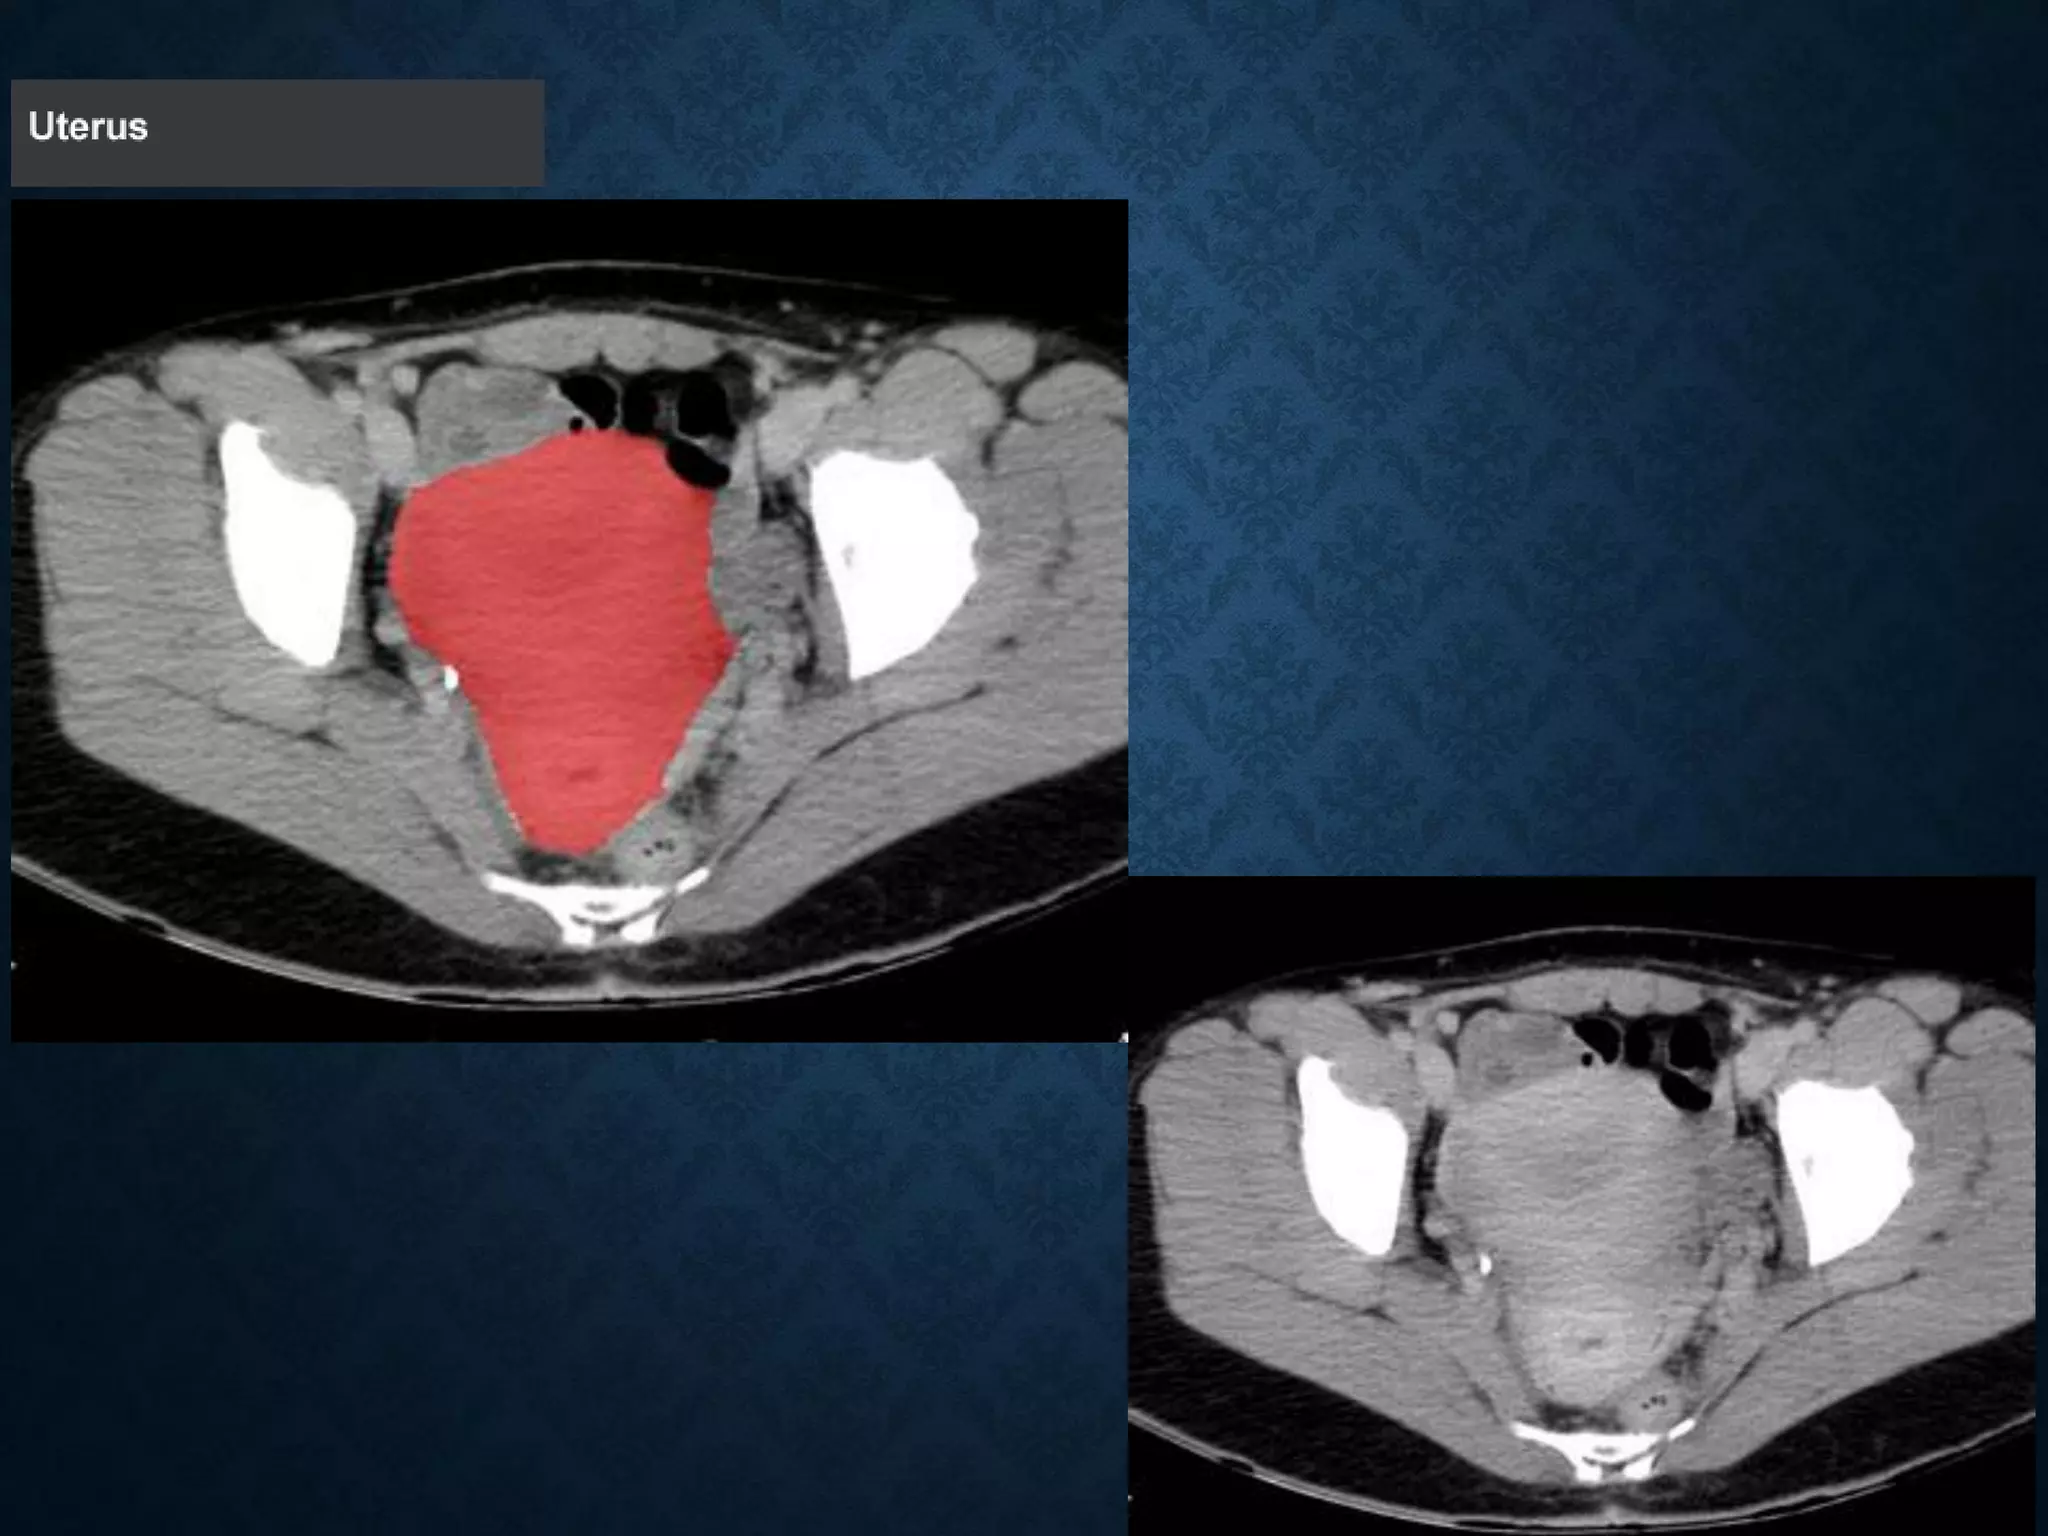

Normal Anatomy- Section 14 (female)

OVARIES